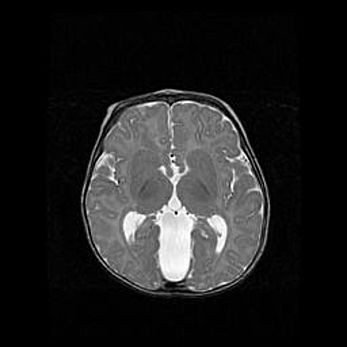

Сообщающаяся гидроцефалия. Кистозная энцефаломаляция головного мозга.

Возраст: 3 месяца 4 дня

Вес: 3100 г

Пол: женский

Окружность головы: 34 см

Срок гестации: 31 неделя

Кистозная энцефаломаляция головного мозга - одна из форм поражения головного мозга в детском возрасте. Характеризуется возникновением множественных и распространённых кист в коре, белом веществе и подкорковых образованиях головного мозга у плодов, новорождённых и детей раннего возраста. Развитие кистозной энцефаломаляции связано с внутриутробной асфиксией и гипотонией, родовой травмой, тромбозом синусов, пороками развития сосудов, инфекциями, сепсисом и другими причинами. Наиболее значимые инфекционные агенты: вирусы простого герпеса, цитомегалии, краснухи, токсоплазмы, энтеробактерии, золотистый стафилококк и другие.